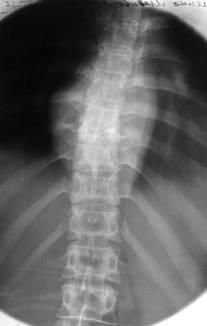

У поперековому відділі абсцес поширюється в поперековій м'язі, зображення зовнішнього контуру якої на рентгенограмі в прямій проекції стає опуклим і асиметричним при порівнянні із симетричною м'язом (рис. 10).

Мал. 10. Спондиліт з частковим руйнуванням міжхребцевого диска L3-4 і контактної деструкцією в суміжних відділах тіл хребців. Розширено межі поперекових м'язів за рахунок псоа-абсцесів (стрілки).